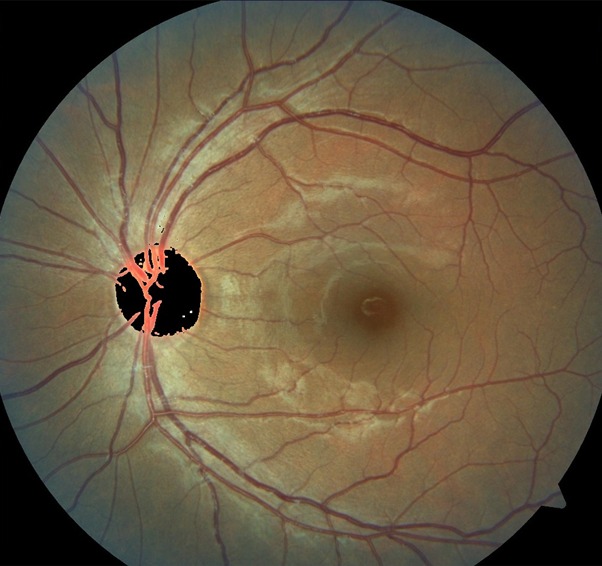

"Con este software que estoy haciendo, extraigo las venas, las aisló completamente del ojo y el médico puede hacer un análisis más detallado solo de las venas y también extraigo, exudados, micro aneurismas y las hemorragias en caso de existirlas". Dicho software aún se encuentra en proceso de pulimento.

“Ahora lo que estoy trabajando es en el análisis de imágenes de fondo de ojo. Esas imágenes las clasifico en el grado de la enfermedad que tienen. La idea es hacer esto utilizando una tecnología llamada redes neuronales (subconjunto del machine learning) convolucionales, esto es para automatizar el proceso de detección”.

Con un trabajo enfocado en la retinopatía diabética no proliferativa, y con el propósito de detectar la enfermedad preferentemente en una etapa moderada-leve, el estudiante de posgrado busca proponer un software en el que se pueda integrar toda la información en una aplicación de forma que sea amigable con el usuario final que sería el personal médico:

“La idea de esta aplicación es que muestre los rasgos característicos de esta enfermedad que vienen siendo exudados duros que son como una especie de manchitas amarillas que aparecen en la retina, son muy comunes en pacientes de moderados a severos”. Sin embargo, aclaró que no es algo determinante, sino, auxiliar para él o la profesional médico.